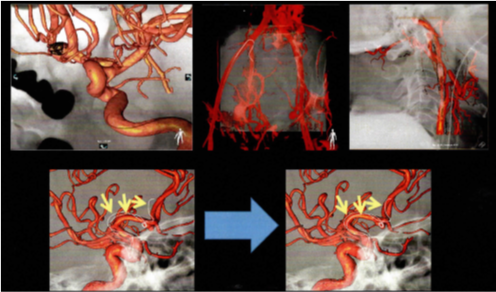

検出器の多列化により短時間に広範囲の撮影が可能となりました。また1度の撮影で様々な断面画像を得られます。得られた画像をワークステーションで解析することで3D画像を作成できます。

造影剤を使用することで病変や血管を詳細に描出できるため病変部の血管走行を把握することができます。血管走行の3Dは手術プランに役立てられます。- 腰部血管3D

- 頭部動静脈3D